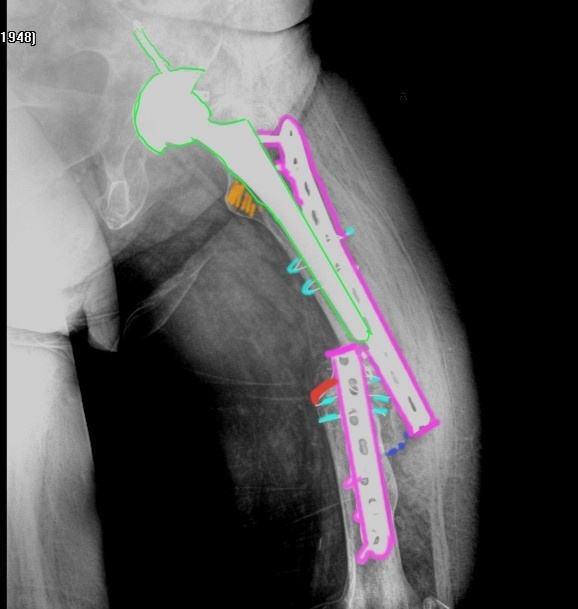

Классификация переломов диафиза бедренной кости: Иллюстрации и информация